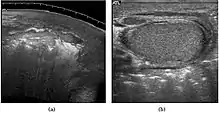

Fig. 29. Undescended testis. (a) Normal testis in the scrotum. (b) Atrophic and decreased echogenicity of the contralateral testis of the same patient seen in the inguinal region.